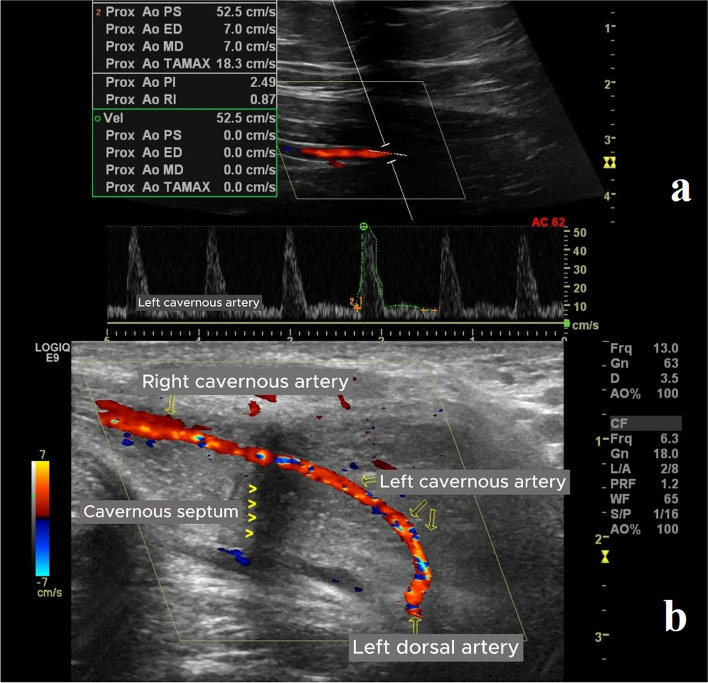

Methods: This study included a total of 35 patients who underwent penile revascularization. Penile color Doppler ultrasonography was performed preoperatively and at the third postoperative month to evaluate cavernosal arteries, dorsal arteries, deep dorsal vein, and inferior epigastric artery. During these evaluations, peak systolic velocity, end diastolic velocity, and resistive index were measured. The International Index of Erectile Function questionnaire was administered before surgery and at the third postoperative month. In addition, corpus cavernosum electromyography and cavernosometry tests were performed in all cases preoperatively. Anastomotic patency was assessed using computed tomography angiography at the end of the follow-up period.

Results: The mean preoperative resistive index values were determined to be 0.74 ± 0.07 and 0.73 ± 0.09 cm/s for the right and left cavernosal arteries, respectively, and these values increased to 0.95 ± 0.09 and 0.96 ± 0.06 cm/s, respectively, at the last postoperative control. The mean International Index of Erectile Function-5, 15 scores for the right and left cavernosal arteries were 8.52 ± 4.83 and 19.4 ± 8.54, respectively, preoperatively, and these scores improved to 15.26 ± 4.50 and 35.76 ± 13.65, respectively, at the last postoperative follow-up.